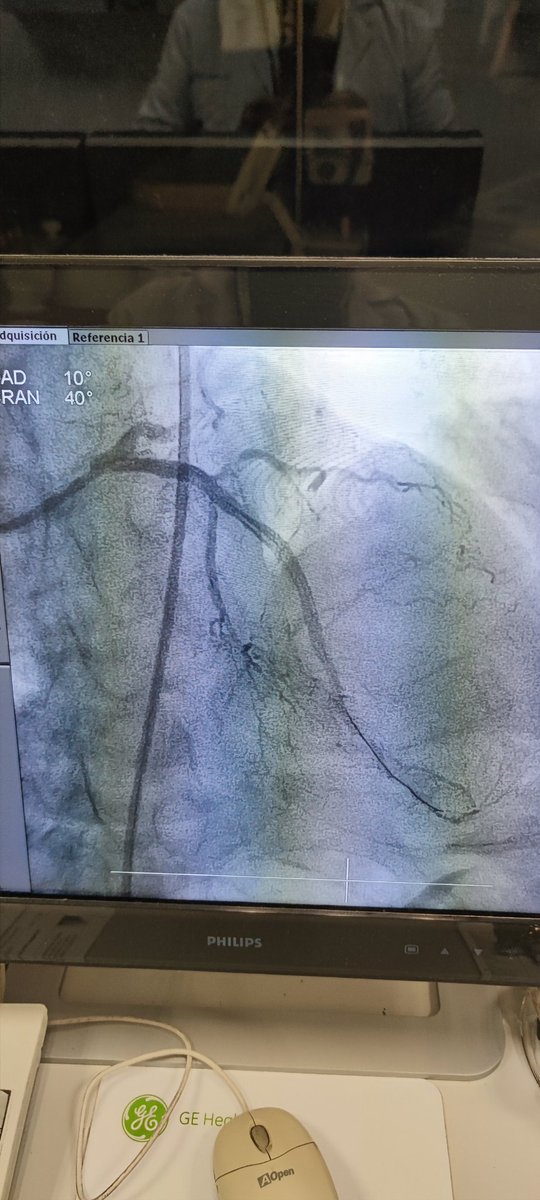

🫀⚡🧔🏻 45a, 🚬intenso, sedentario, obeso, HTA, #SICA #RadialFirst angio CD OTC agudizada TM disección ostial, Fullmetal CD 👌🏼 #MasterTheComplex #PCI #IVUS #Terumo #Azahi #BostonScientific #Medtronic